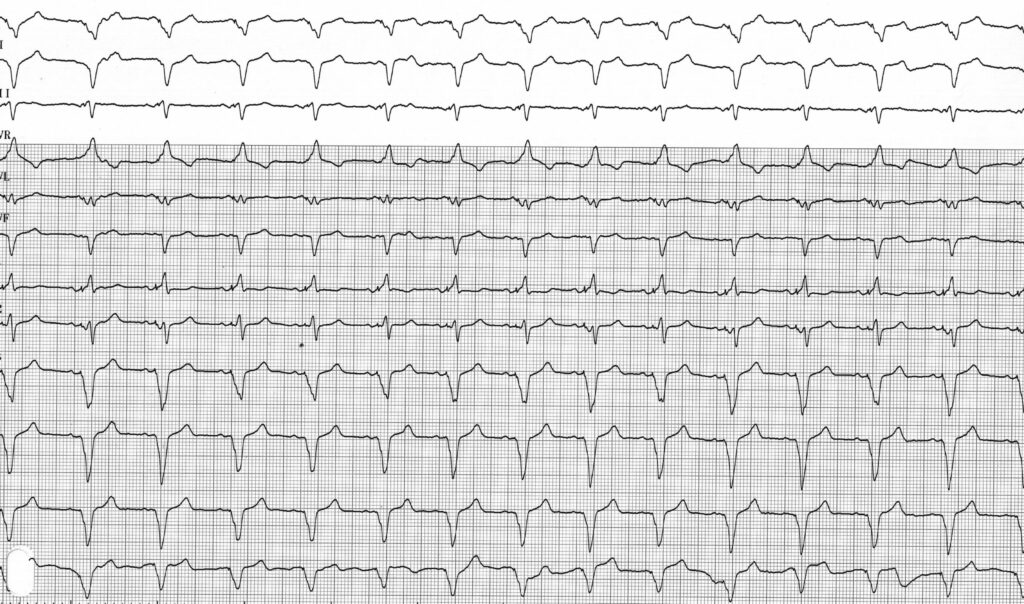

Description tracé

Tracé enregistré après programmation d’une stimulation ventriculaire gauche seule; aspect du QRS beaucoup plus large que lors de la stimulation biventriculaire avec négativité franche en DI et positivité en V1 compatibles avec la position latérale de la sonde;